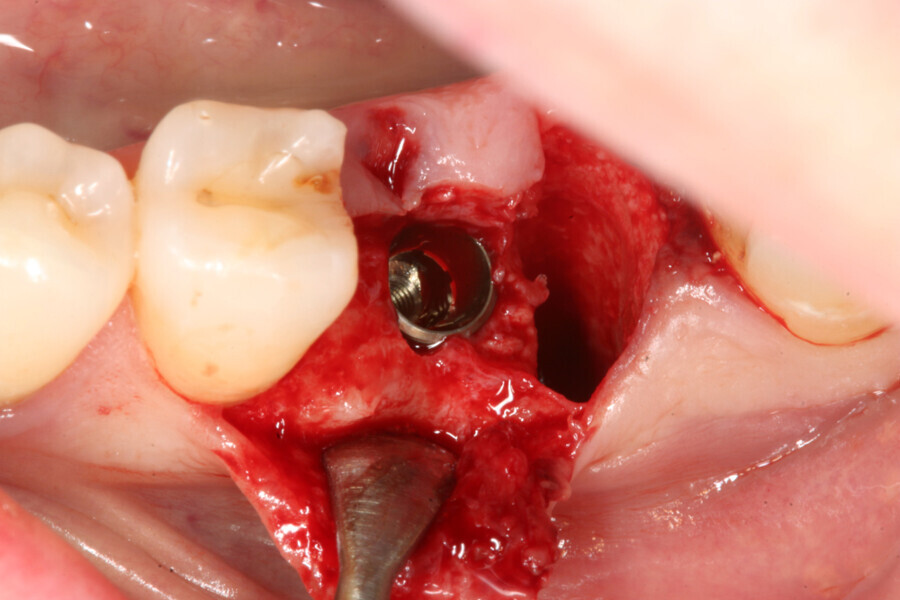

The implant site was prepared following the recommended drilling protocol for the planned PrimeTaper EV 4.2 mm diameter implant (drills #1, 3 and 4; Fig. 2). After cortical preparation with drill #5, the implant was placed. The preparation was finalised with a tap, owing to dense trabecular bone (Fig. 3). The implant was inserted to a torque of 42 Ncm (Fig. 4).

Immediately after implant placement (Fig. 5), the abutment position was registered with an intra-oral scan using Primescan (Dentsply Sirona; Fig. 6). At the end of the surgical procedure, the socket was grafted with Symbios (Dentsply Sirona) and a healing abutment was seated (Fig. 7). Radiographic evaluation was performed on the same day (Fig. 8). On basis of an intra-oral scan, an Atlantis abutment and Atlantis provisional crown were designed and fabricated with an Atlantis IO FLO (Fig. 9).